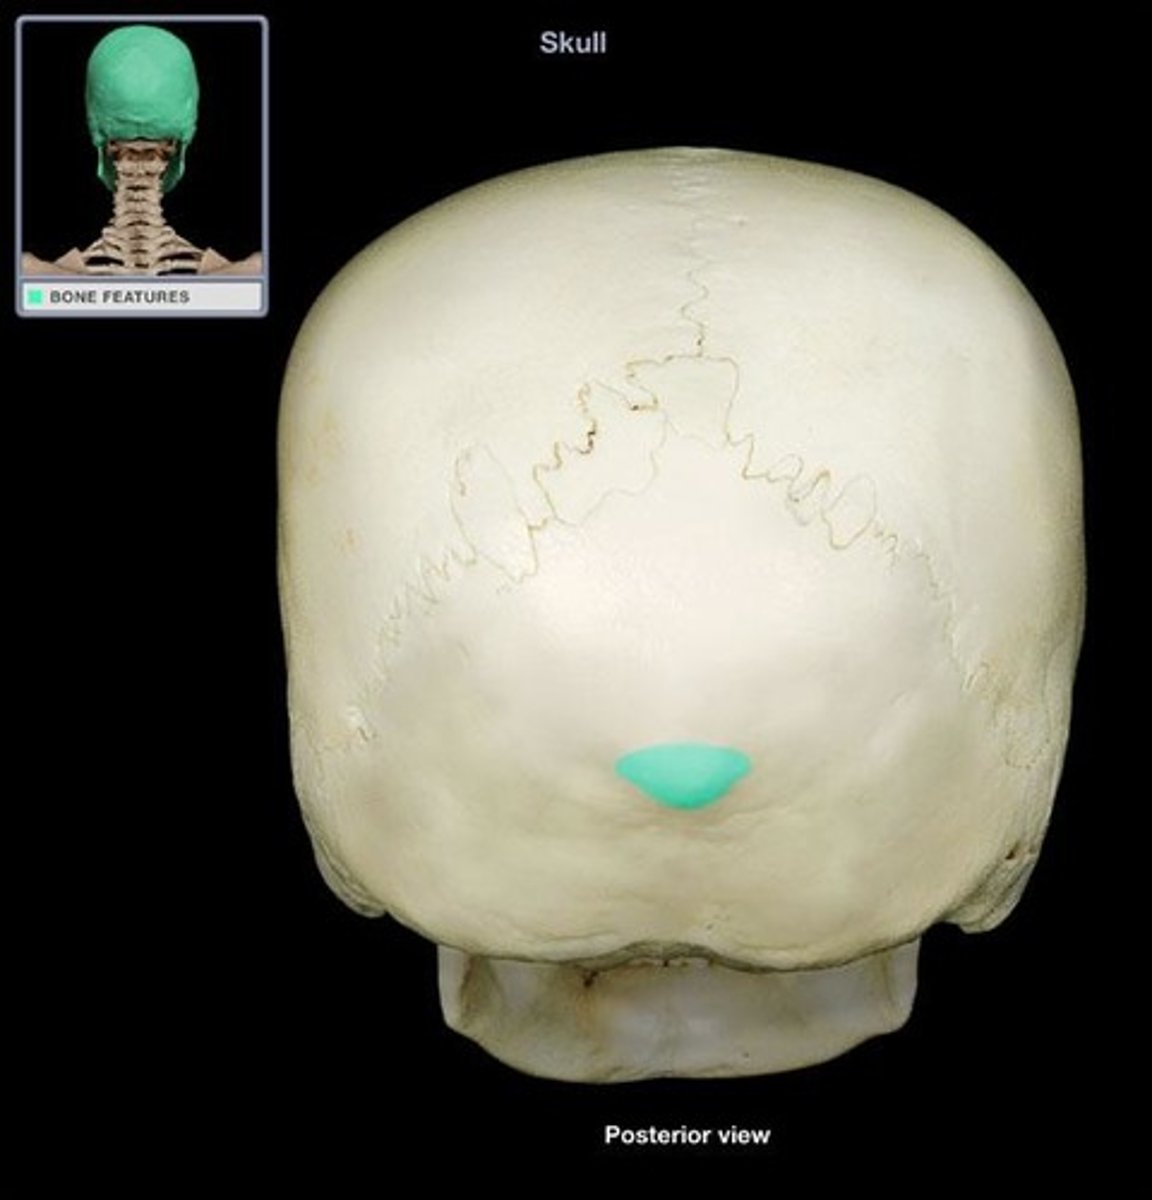

Superior/Inferior Nuchal lines

lines in the back of your occipital lobe

External Occipital Protuberance